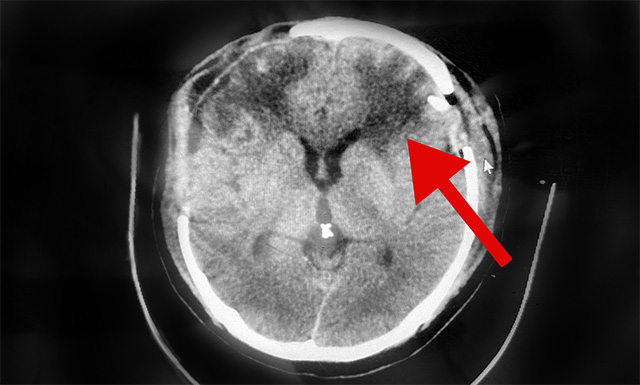

10月4日,经与神经外科6A病区侯增欣主任会诊后认为,患者赵先生右侧硬脑膜下血肿虽已清除,但CT检查显示其左侧硬脑膜下仍存在较大面积血肿,颅内压高,非常危险随时形成脑疝,必须马上手术。

▲术后CT示:患者左侧脑内血肿已清除